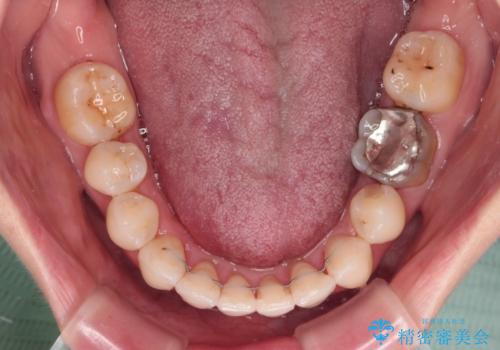

- 奥歯のむし歯を気にして来院された患者様です。

当初は右下の虫歯治療のみを希望されていましたが、虫歯治療に際して部分矯正が必要であったため、治療方法について説明をすると、全体的に歯列不正が気になっているとのことで、全顎矯正を検討することとなりました。

口元の突出感とデコボコがあり、上下左右の小臼歯4本を抜歯して矯正治療を行う方針としました。(右上は欠損のため計3本抜歯)

むし歯となっている歯は状態が悪く、将来的に抜歯となる可能性が高かったため、定石で抜歯させる小臼歯の代わりにむし歯となっている大臼歯を抜歯し、ワイヤー装置にて矯正治療を行うこととしました。